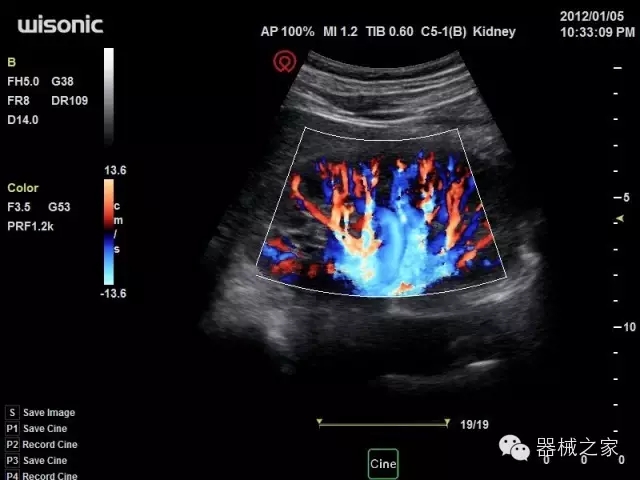

臨床圖片賞析

·獨(dú)有的HoloTM PW 實(shí)時(shí)3取樣門PW成像技術(shù),精確進(jìn)行血管診斷;